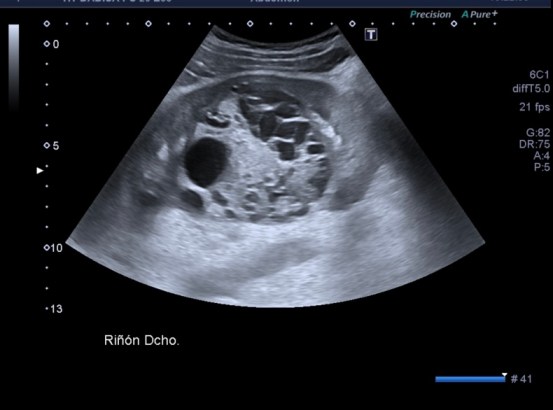

Lesión heterogénea, en el meso-riñón derecho, redonda, típica de quiste hidatídico.

Después de ver esta maravilla de imágenes, habiendo repasado el post 262 donde te explico las claves del quiste hidatídico, no tengo nada más que decir. Las imágenes hablan por si mismas. Perfectas, con una calidad increíble, el equipo increíble, bien ajustado, los parámetros adecuados, es un estudio perfecto, Sandra…yo lo sabía y te lo decía y estoy orgulloso, muy orgulloso de hacer esto que estoy haciendo ahora, en el día 2.

Un quiste hidatídico renal, maravilloso.